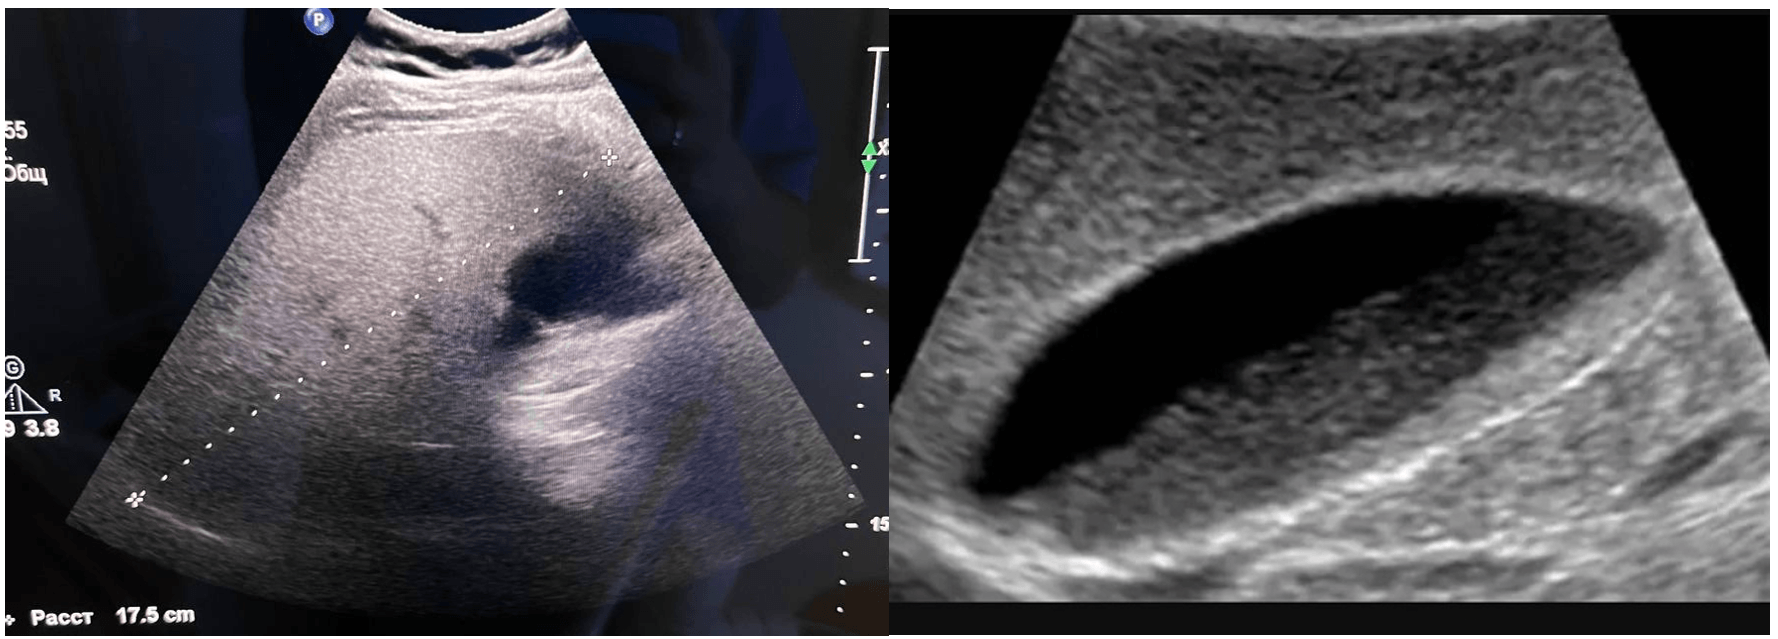

transabdominal ultratovush tekshiruvi paytida quyidagilar aniqlandi:

Ultratovush shifokori uchun asosiy fikr : Odatdagi joylarda - o't pufagi yo'lida yoki porta hepatisda saqlanib qolgan parenximaning "orollari" ( gipoexoik zonalar) mavjudligiga e'tibor bering . Bu holda ular yo'q, bu jarayonning tarqoq tabiatini tasdiqlaydi.

Ultratovush xulosasi:

Alkogolsiz yog'li jigar kasalligi ( steatoz ) turiga qarab jigar parenximasida aniq gepatomegaliya va diffuz o'zgarishlarning exografik belgilari . Safro yo'llarining diskinezi ( safro yo'llari ) loy ).